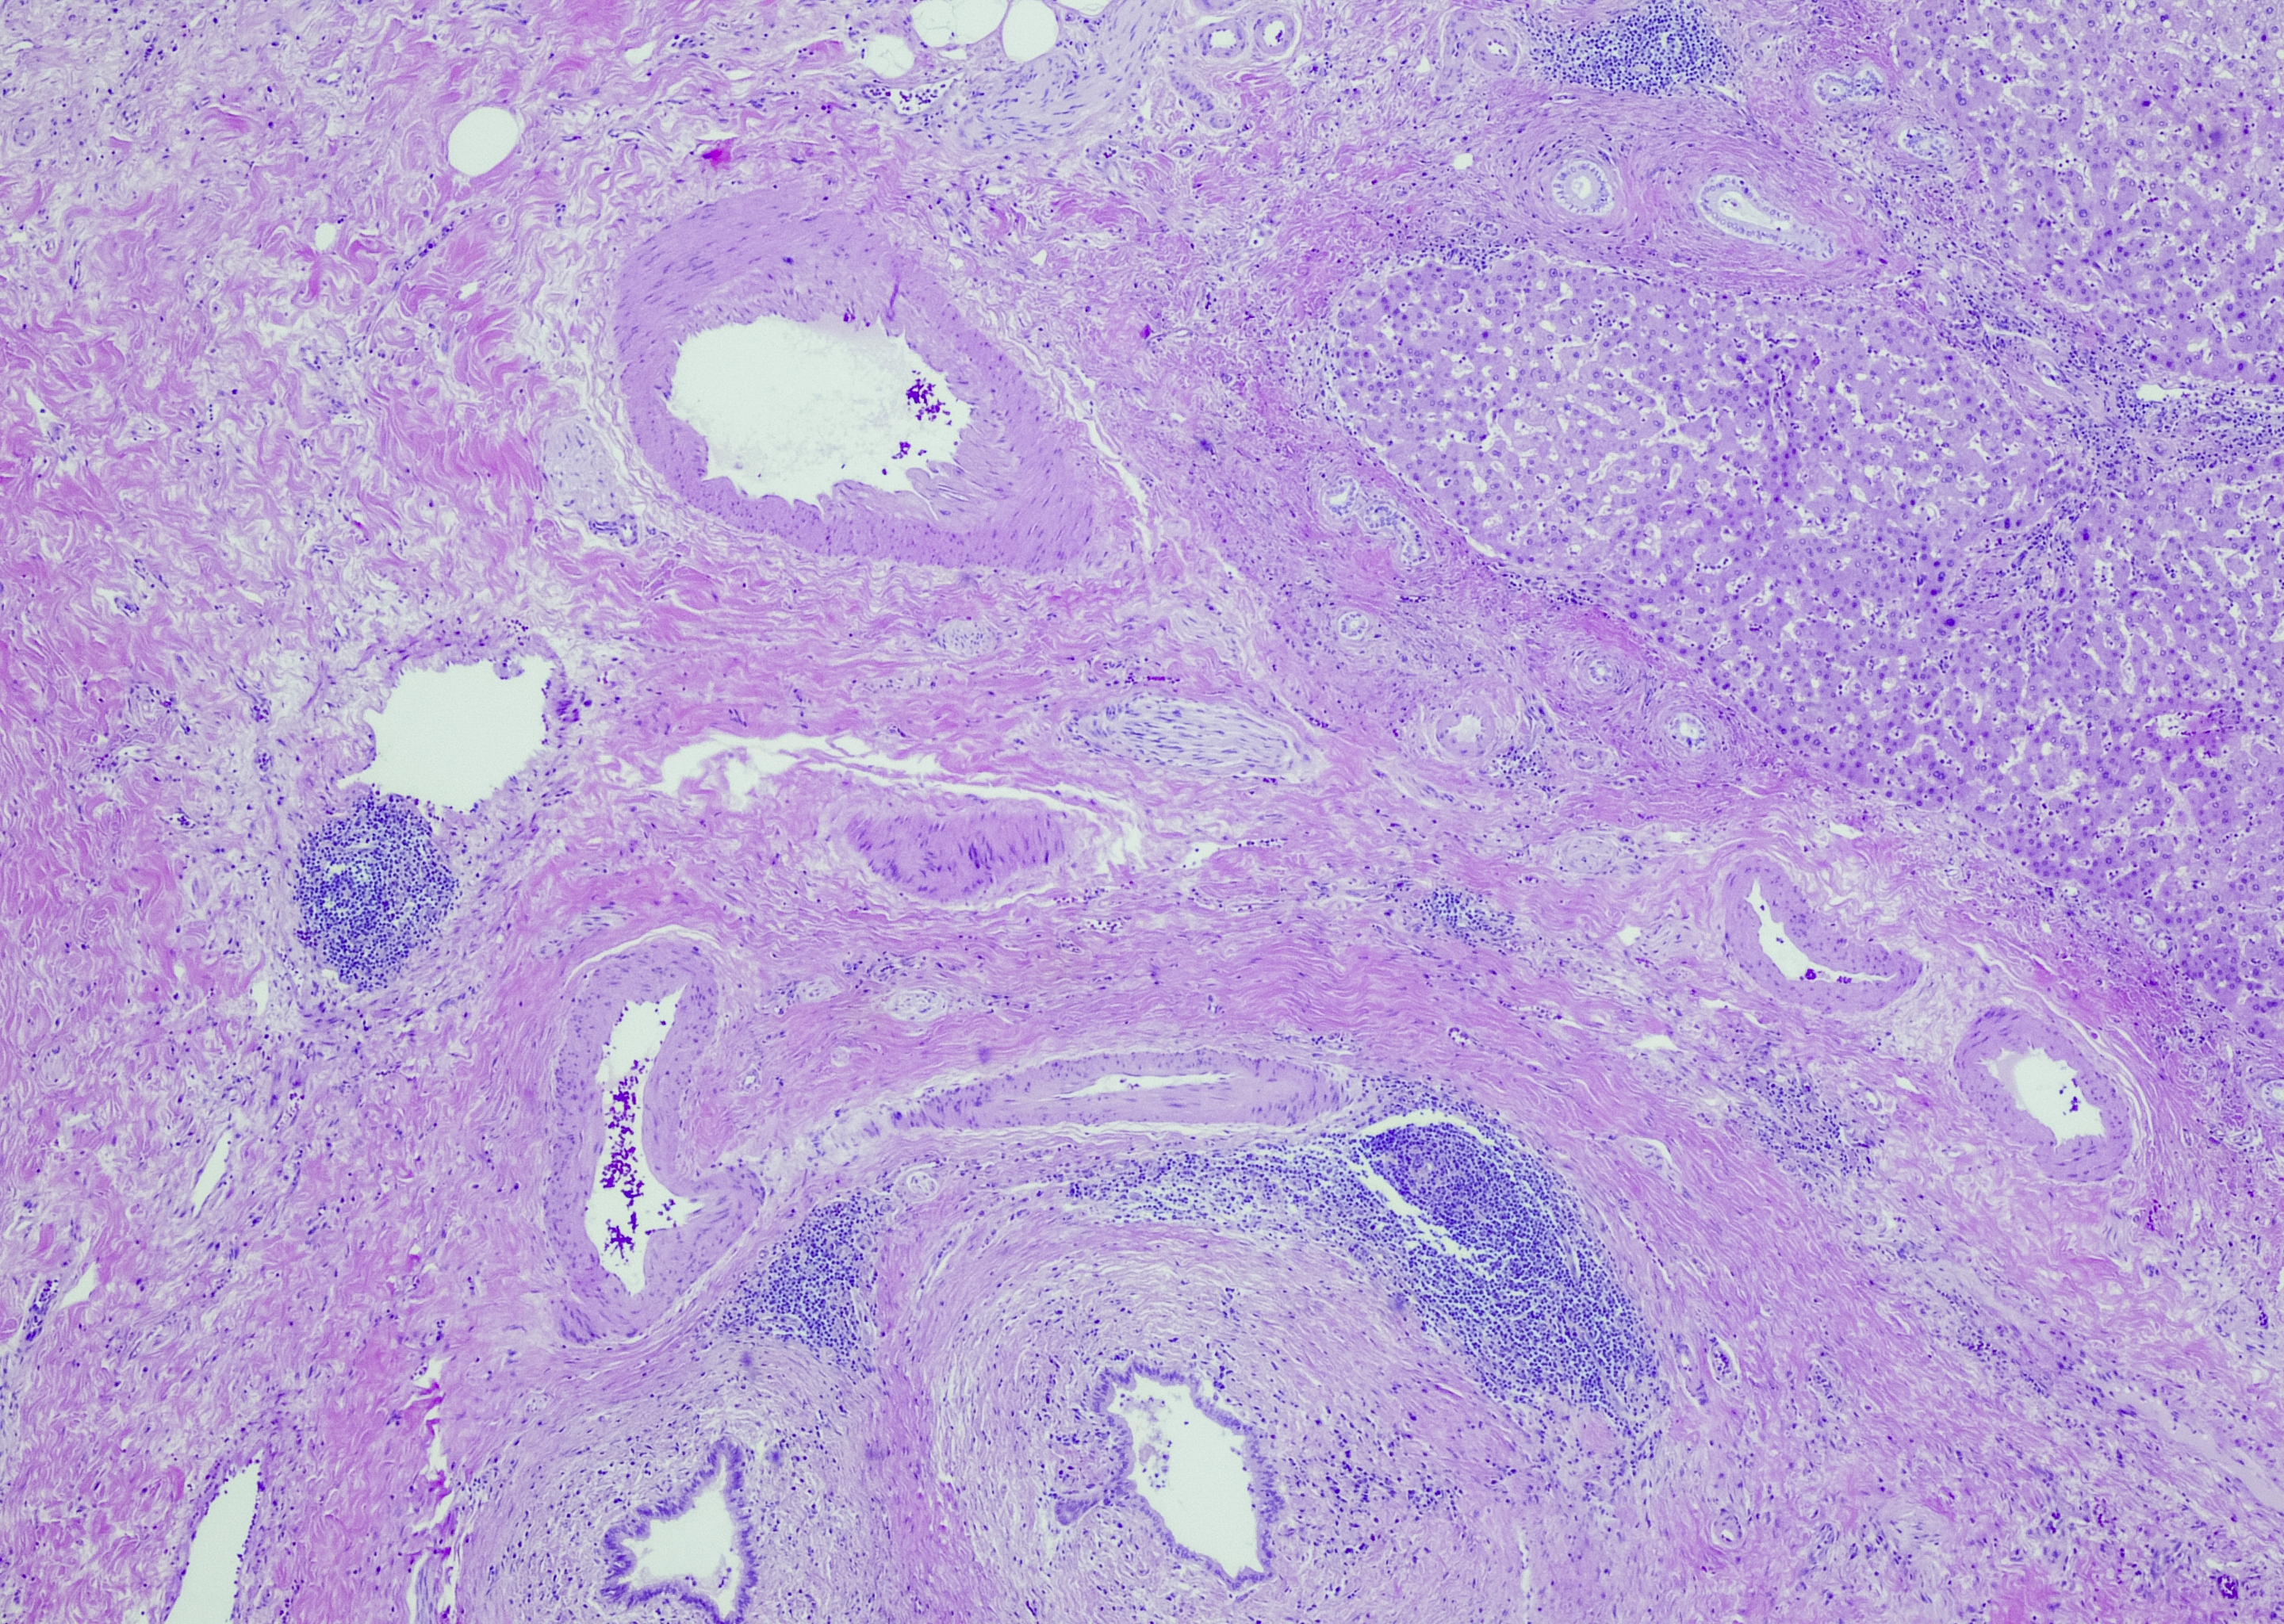

Leverbiopsi er nødvendig ved normal kolangiografi med god billedkvalitet og fortsatt mistanke om primær skleroserende kolangitt. Undersøkelsen kan avdekke differensialdiagnoser og en undertype av sykdommen som affiserer de små intrahepatiske galleveiene, og som vanligvis har et mildere sykdomsforløp (small-duct primær skleroserende kolangitt) (2).